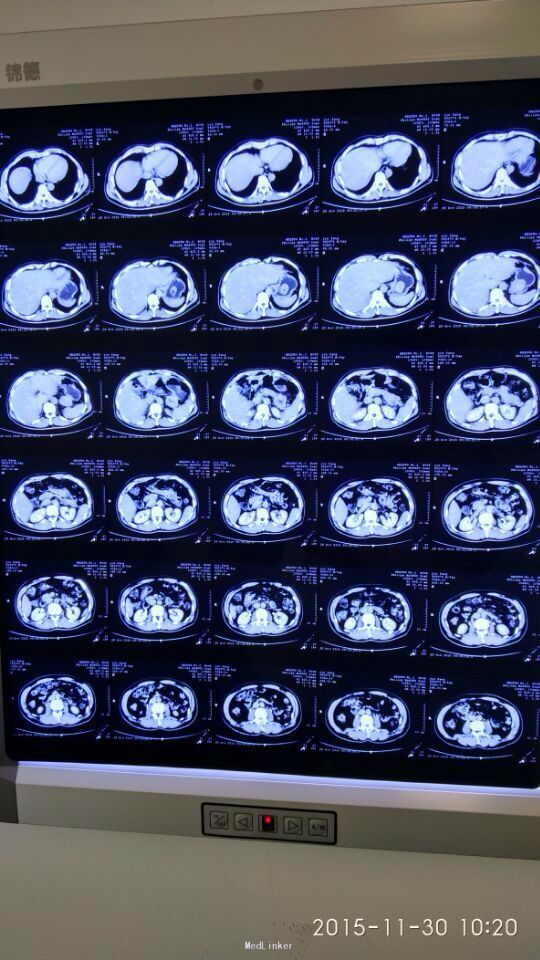

间断性上腹部隐痛,加重两月余。 于15年前左上腹间断隐痛,可忍,伴肩背部放射,活动后缓解,无恶心呕吐,大小便正常,未行特殊处理。2月前,上述症状出现并加重,伴腹泻,伴肩背部放射,无皮肤粘膜黄染。

胃间质瘤 拟行胃间质瘤切除术

瘤体较大,超过5cm,术中注意与胰腺关系,如果压迫胰腺或压迫脾脏血管,是否考虑部分胰腺切除及脾切除,是否考虑胃空肠吻合。